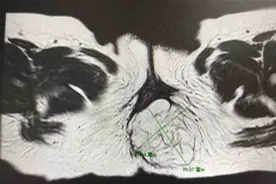

新生儿外科郑锦涛博士介绍,骶脊髓脊膜膨出是新生儿外科疾病之一,发病率约为1/1000-3/1000,一般正常脊髓圆锥水平,随着发育会逐渐向上移,该病如果不治疗则会发生脊髓牵拉现象,临床上称为脊髓栓系综合征,会引起双下肢瘫痪、大小便失禁等严重后果,手术是治疗该病的唯一手段。